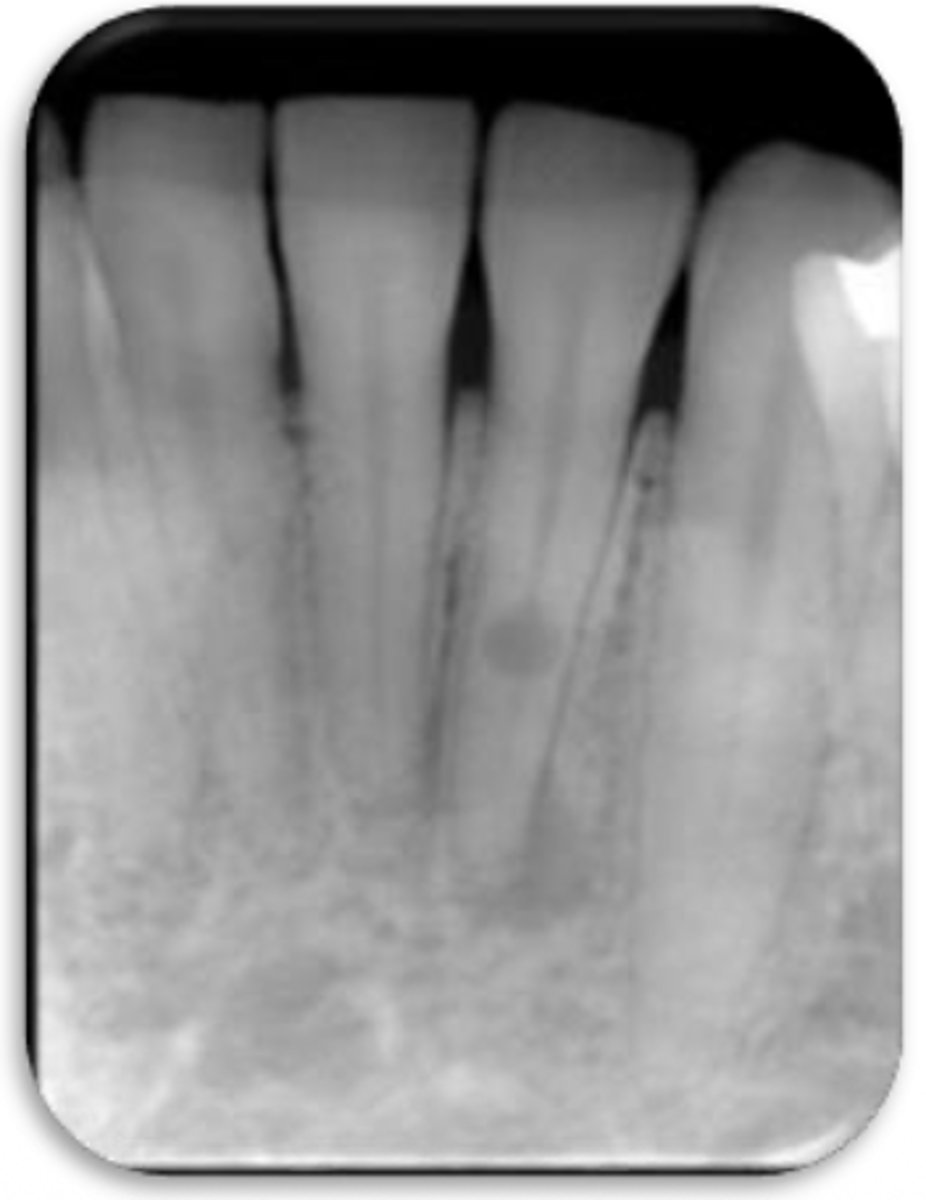

ID the problem:

splitting canals